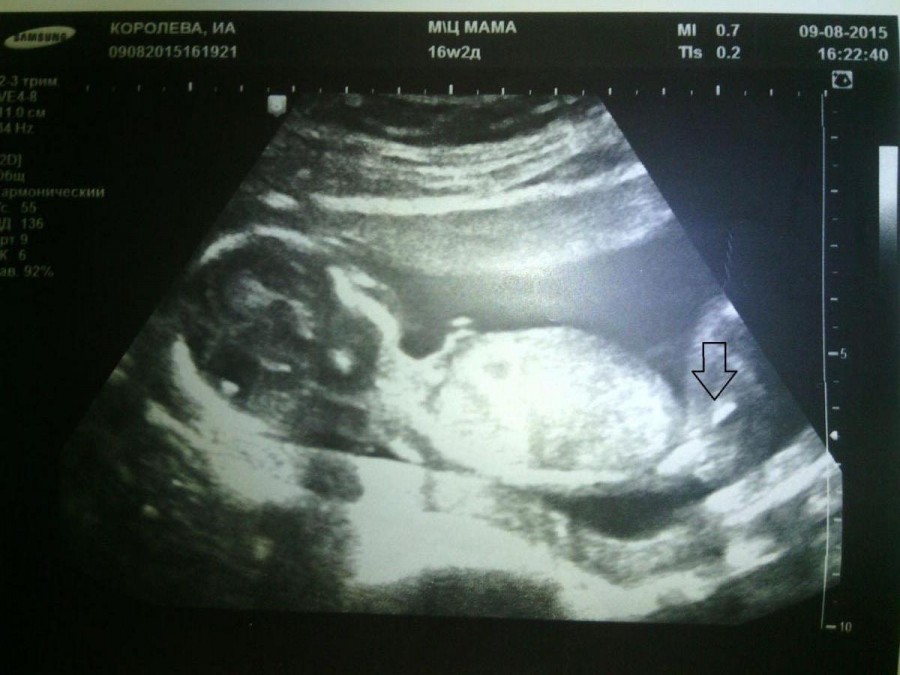

Какие параметры фиксируются во время УЗИ

- окружность головы и живота;

- длина бедренной и плечевой кости;

- предполагаемая масса плода;

- примерный объем околоплодных вод;

- положение плаценты (прикрепление к передней или задней стенке);

- прикрепление пуповины, количество сосудов и кровоток в них;

- сердцебиение плода;

- длина шейки матки.

Эти данные помогают оценить скорость развития плода в соответствии со сроками беременности, выявить генетические патологии, риски угрозы прерывания.